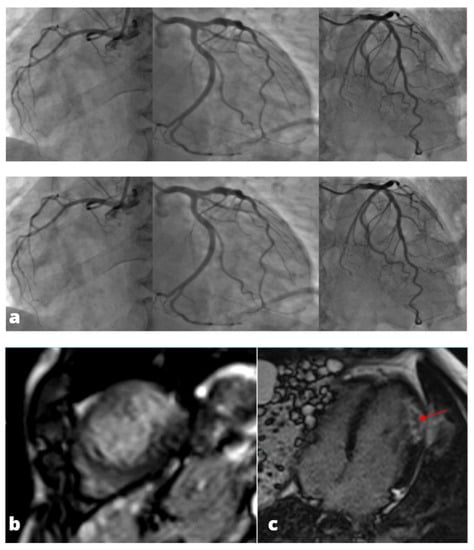

Figure 1.

A young adult presenting at emergency department with acute chest pain, subtle ST alterations in the lateral wall of the left ventricle and cardiac enzymes elevation. Cardiac MRI was performed 48 h later demonstrating edema in the inferior-lateral wall of the left ventricle (a) associated with hyperemia in early gadolinium enhancement (b) and post-inflammatory fibrosis using late gadolinium enhancement sequences (c).